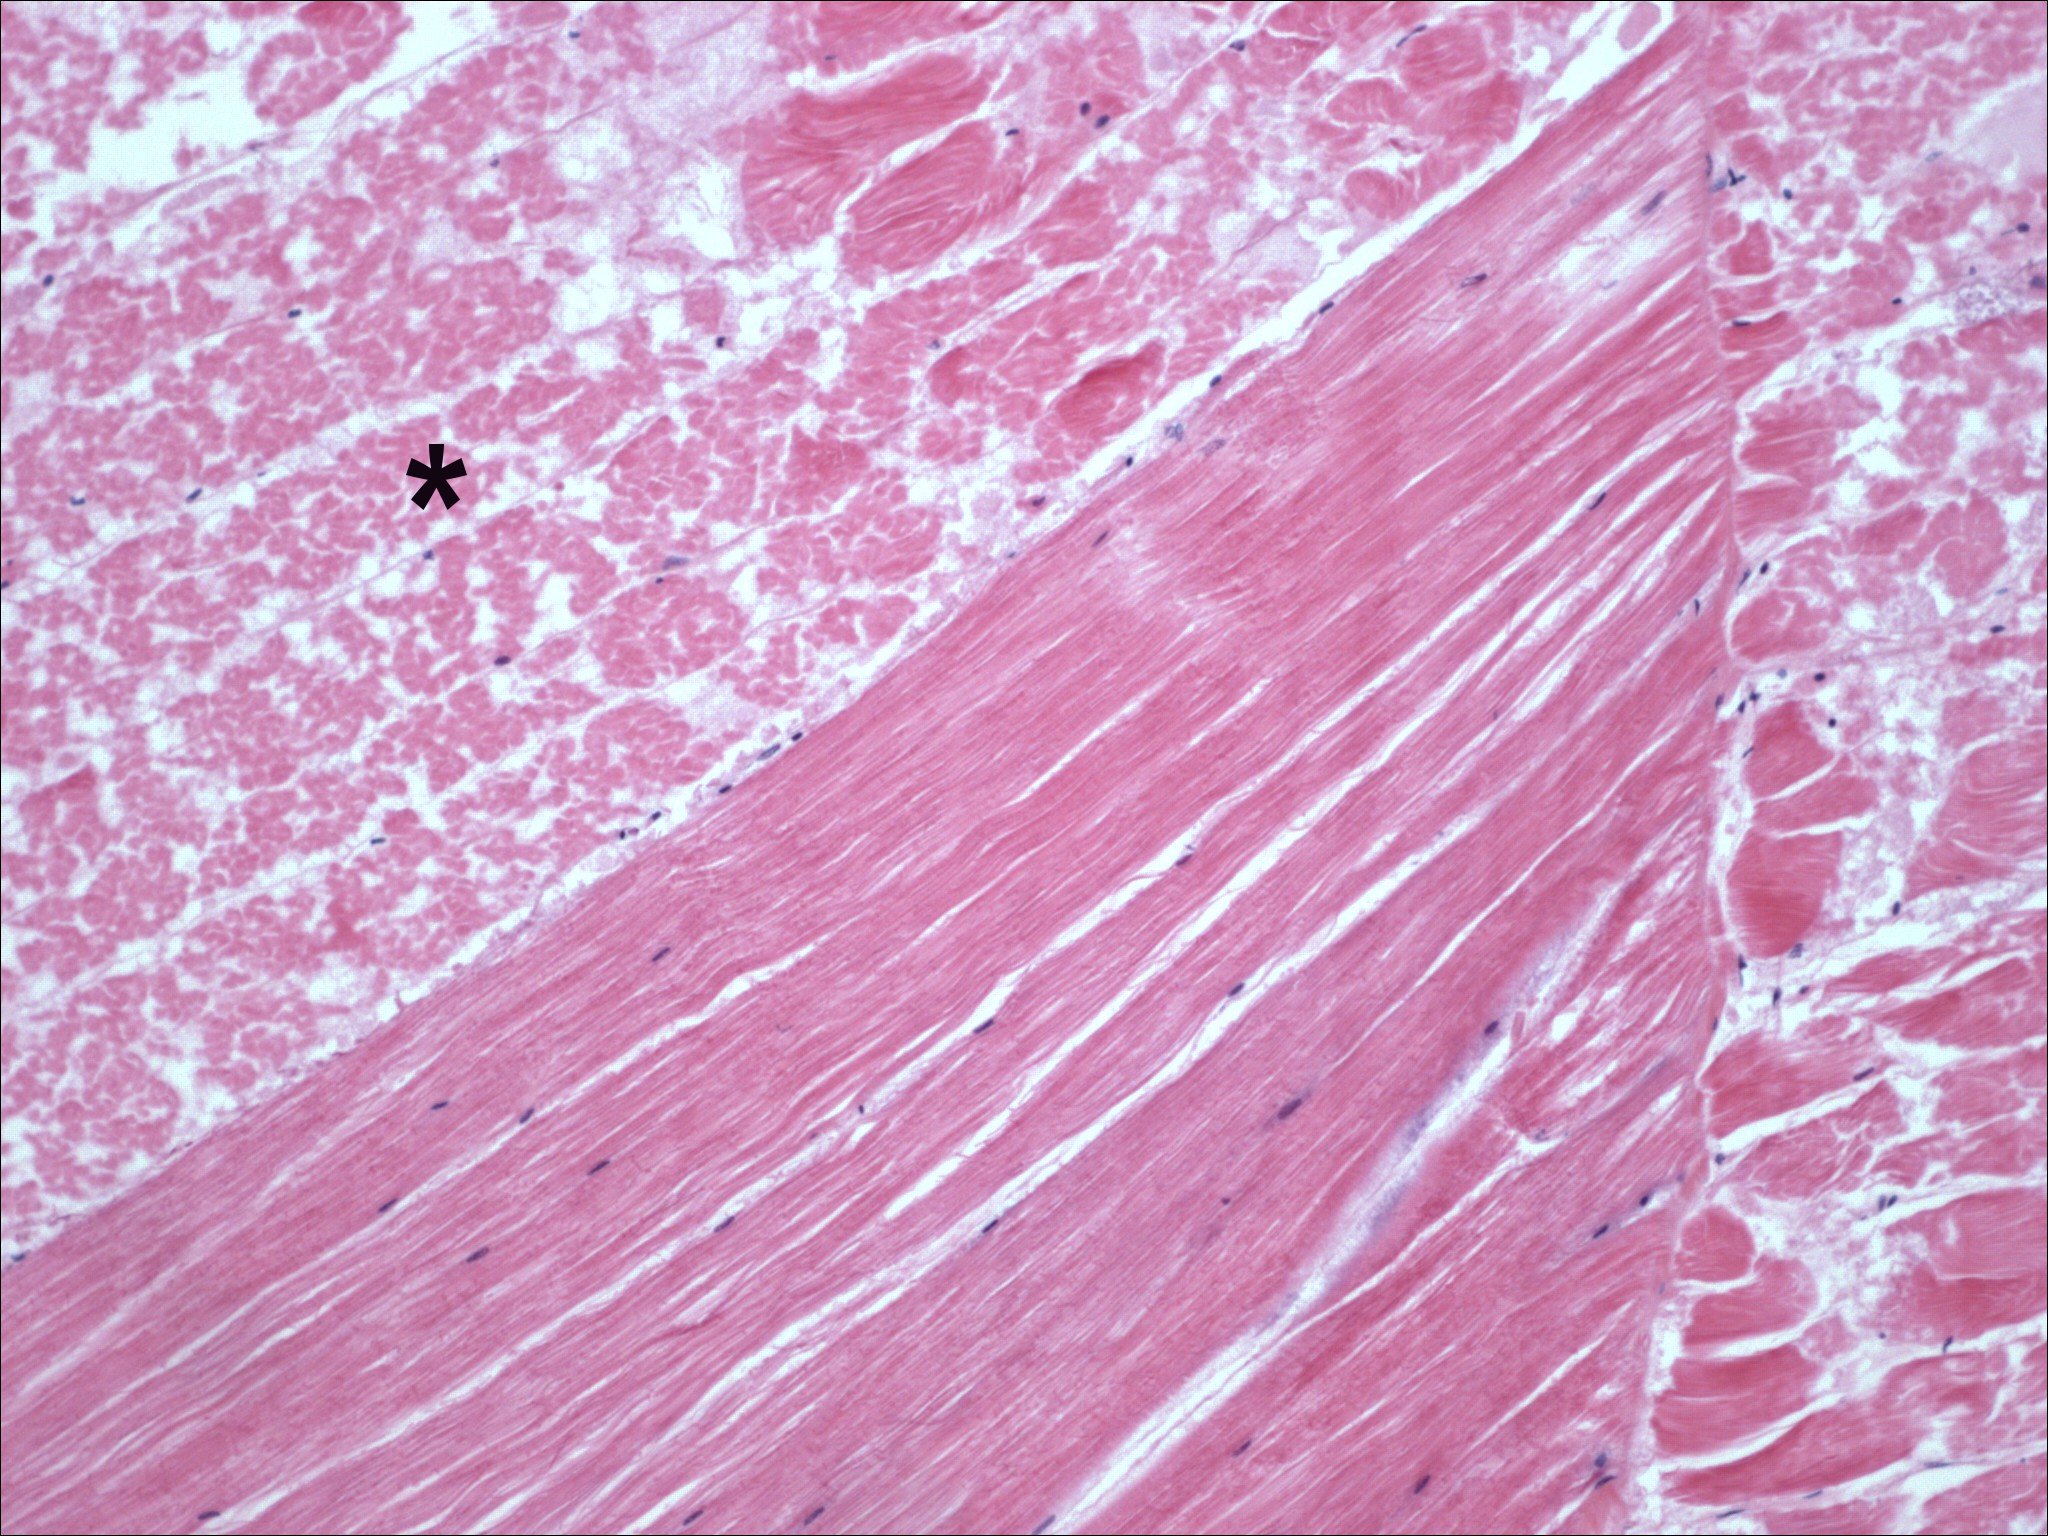

Muscle

Focal acute muscle necrosis with oedema, haemocytic inflammation and fibrosis.  Enlarged Lymphoid organ with spheroids, spheroids can become ectopic and be found in gills and heart